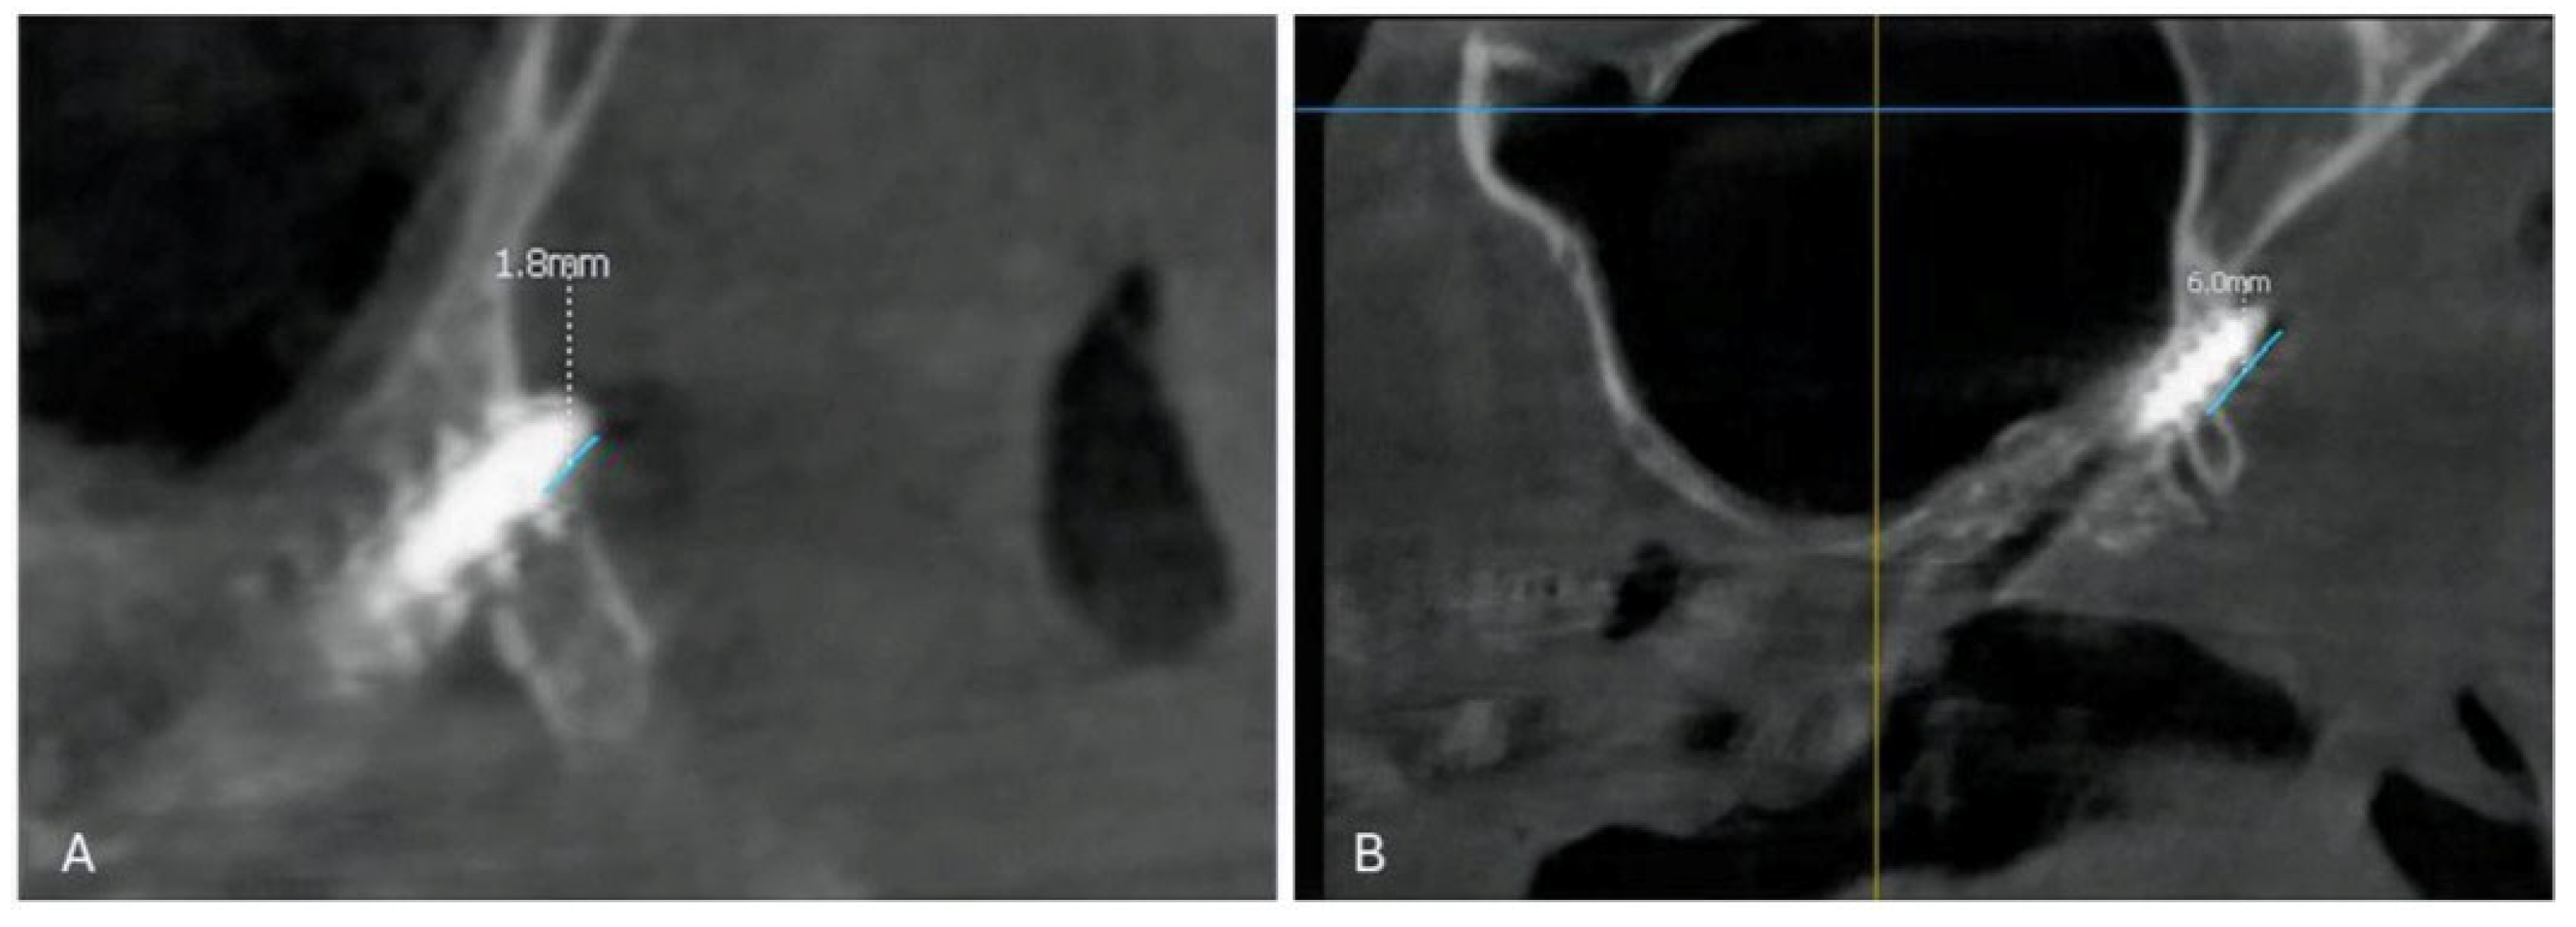

2.3. Imaging and Measurements

3.2. Distribution of Penetration Depth